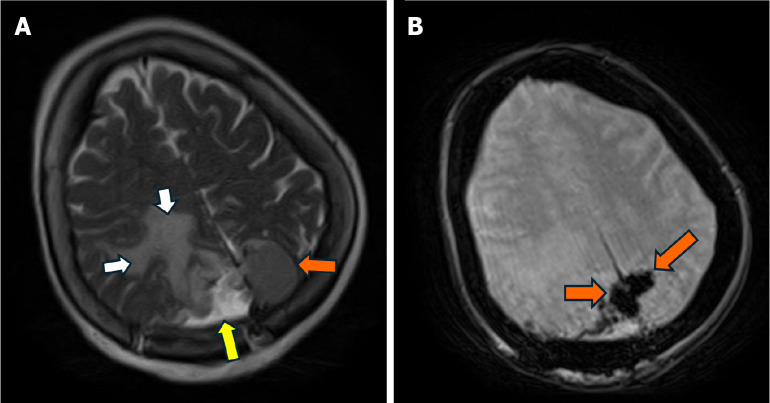

Case summary: We present a case describing a 78-year-old female who came in following a ground level fall. The primary assessment was notable for a history of similar recurrent falls and subtle left-sided peripheral visual field loss. Further neurological examination was otherwise largely unremarkable. A computed tomography scan of the head revealed a large extra-axial mass located along the posterior aspect of the falx. Follow-up magnetic resonance imaging confirmed a lesion measuring around 6.6 cm × 4.2 cm × 5.5 cm. A partial surgical resection of the right-sided portion of the lesion was performed. Complete resection was limited by insufficient visualization and challenges with hemostatic control of the left parafalcine region. Further histopathological analysis confirmed a fibrous meningioma with focal necrosis, consistent with World Health Organization Grade 2 classification. She was subsequently scheduled for outpatient follow-up to assess the residual tumor management.